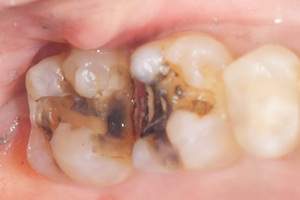

銀歯などの詰め物と歯の隙間から虫歯になっているイメージ

歯とつめ物の間にわずかな隙間ができてくることで虫歯になります。

銀歯は経年劣化しますし、銀歯をくっつける接着剤も劣化します。そのため隙間は年々大きくなる傾向に

あります。

経年劣化していた銀歯

麻布十番歯科で銀歯の症例の口腔内写真

経年劣化していた銀歯の歯

麻布十番歯科で銀歯の中が虫歯になっている症例の口腔内写真